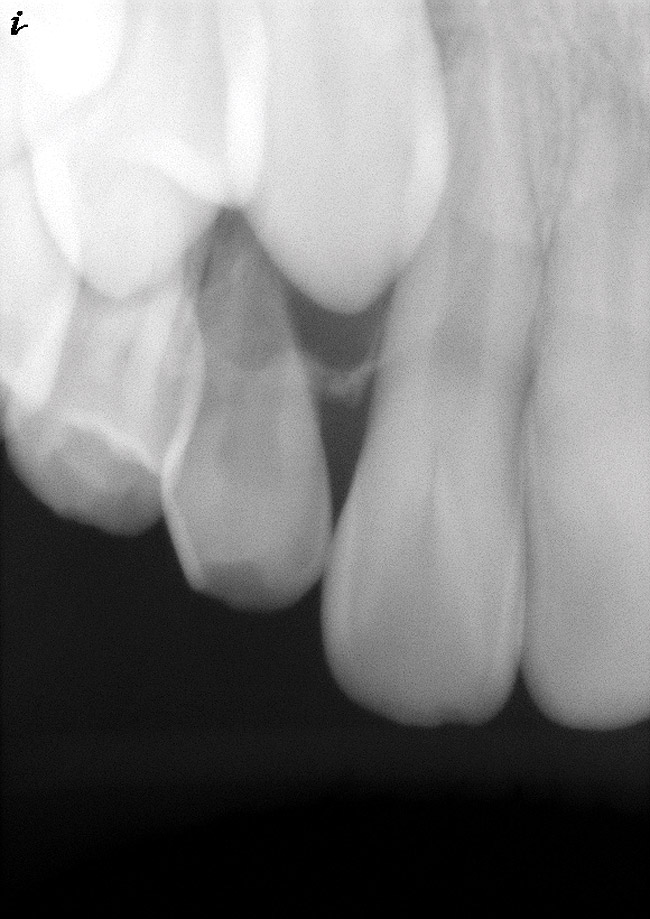

As mentioned, all risk factors associated with both root canal and implant therapy must be carefully considered. Comprehensive clinical and radiographic assessments are necessary to evaluate the patient's risk factors associated with his or her particular case (Figure 1, Figure 2 and Figure 3). The primary risk factors for implants can include smoking, bone quality, and systemic health. For endodontic therapy the primary risk factors are related to the anatomic root complexity, failed root canal treatment with significant technical defects manifested as iatrogenic events, less-than-optimal periodontal status of the tooth (due to a subsequent risk of vertical fracture), and a clinician's lack of experience with regard to the case's complexity. A strong correlation exists between failed root canal treatment and a lack of coronal seal after treatment. This is highly relevant in treatment planning. Often, endodontically treated teeth fail not because they were treated inappropriately and need extraction, but rather, because they have been left unsealed and assaulted by bacteria after the endodontic therapy, causing subsequent long-term clinical failure (Figure 4 and Figure 5).